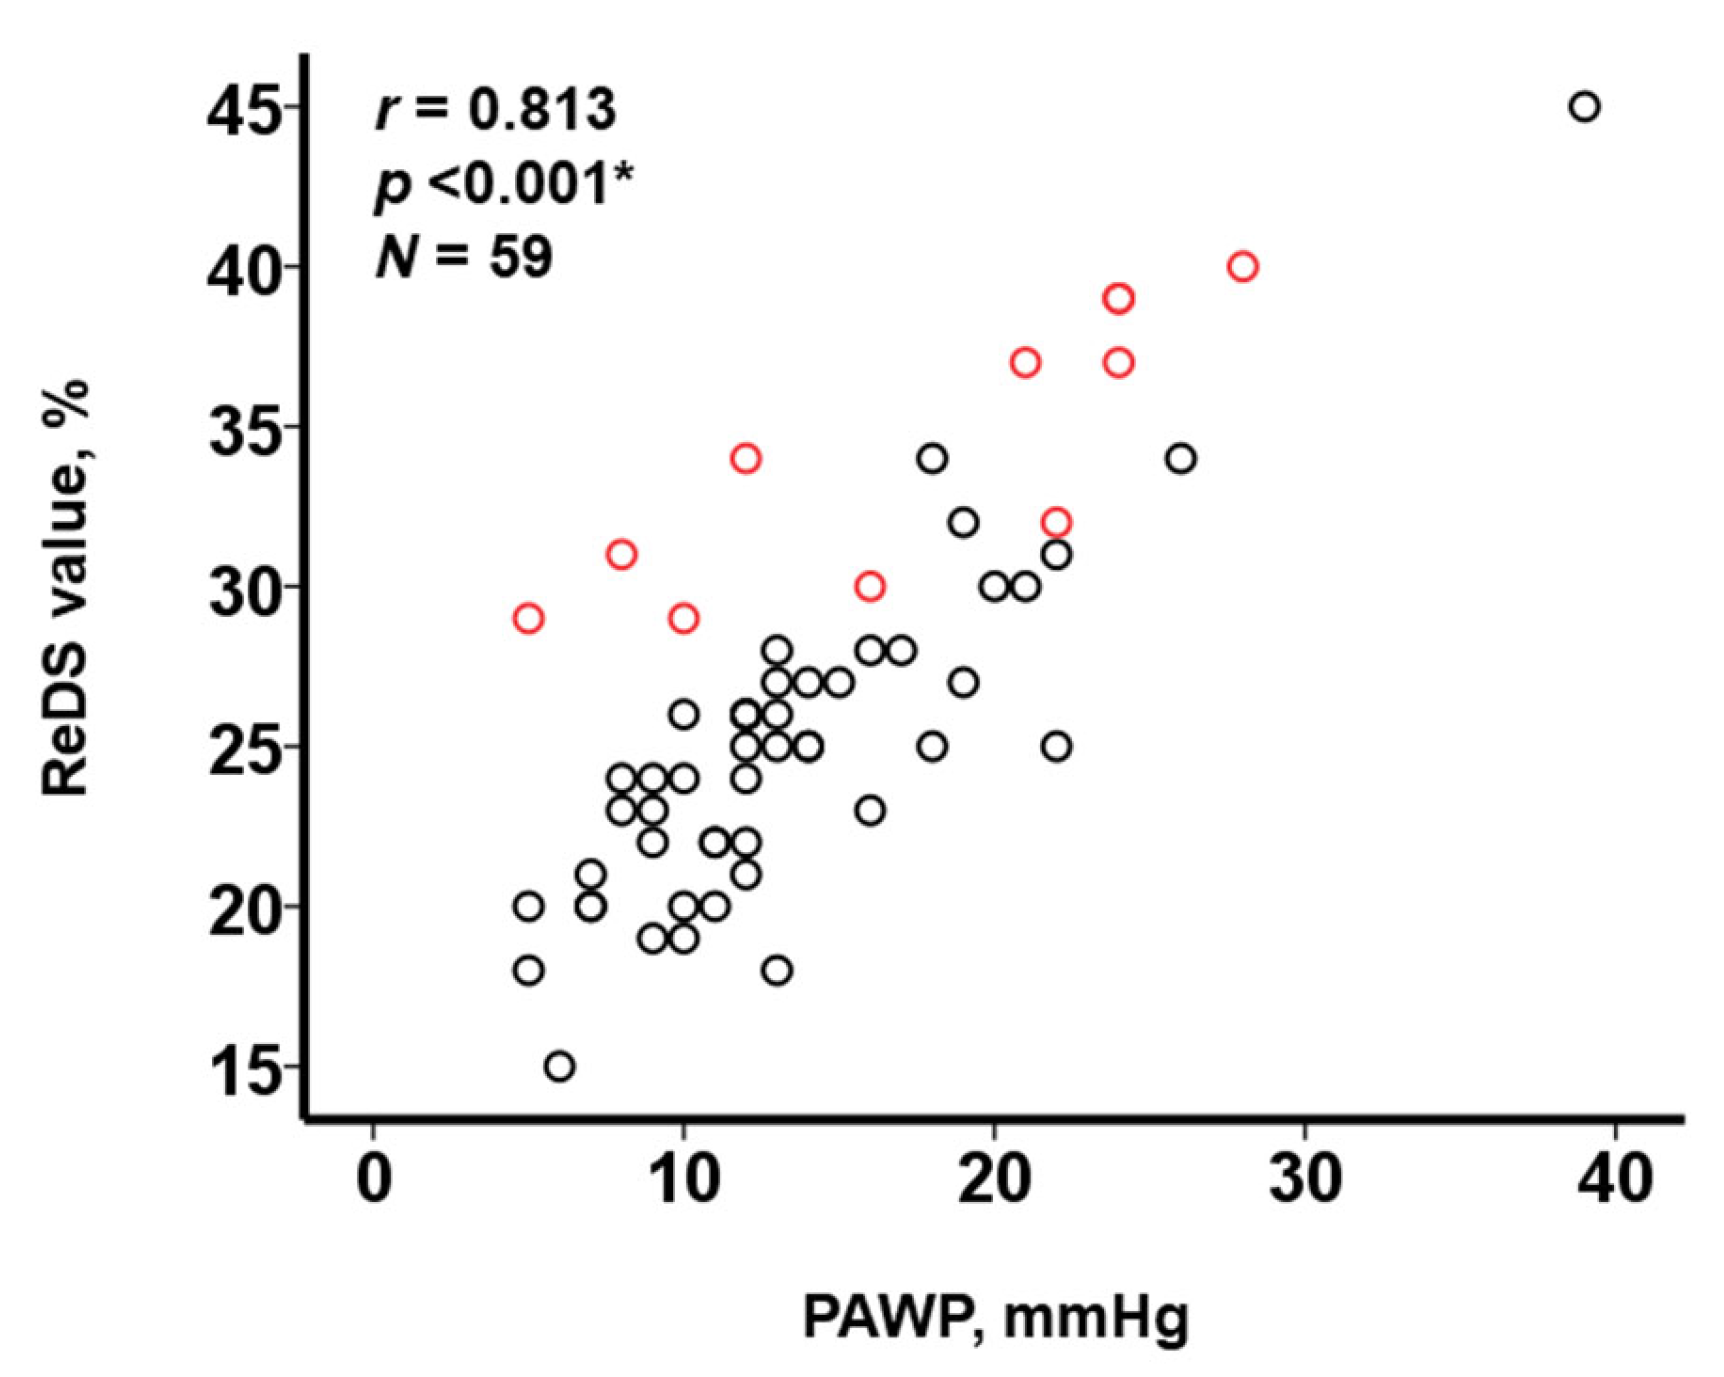

3.3. Impact of PE on the Relationship between ReDS Values and PAWP

4.1. ReDS System to Estimate PAWP Levels

4.2. Impact of the Presence of PE on the Relationship between ReDS Values and PAWP